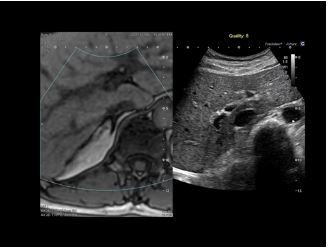

Клінічні зображення

Ультра широкий огляд печінки та нирок надає більше інформації в одній площині.

3D MPR зображення матки в трьох площинах з високою роздільною здатністю дозволяє клініцистам оцінити порожнину матки.